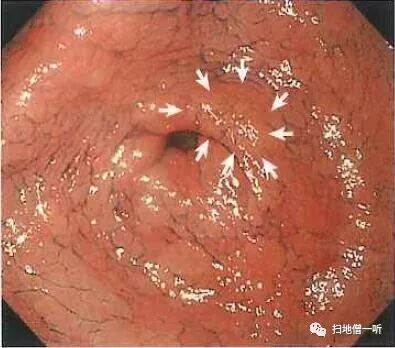

A:胃癌在图3及图6。HP未感染胃癌。

胃粘膜RAC阳性表现,提示HP未感染粘膜。胃体下部小弯侧可见小片状褪色粘膜。图3和图6是两个角度观察同一处病变。

靛胭脂喷洒然后后边界不清,表面无凸凹变化,为IIb型病变。无萎缩的胃底腺区域发现退色调病变,应怀疑印戒细胞癌。

最终病理诊断:

胃体下部小弯,O-IIb,4mm,sig,T1a (M),UL(-)